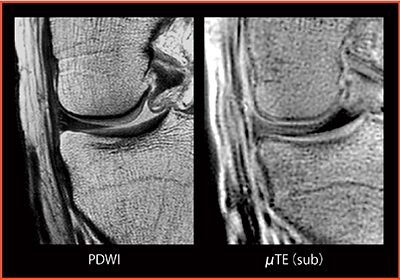

図5 Knee PDWI:μTEサブトラクション法

in phaseで長めのTE=8.8 msで撮像しサブトラクションする。拡大すると軟骨の信号が明瞭に描出されていることが認められ,診断能向上が期待できる。